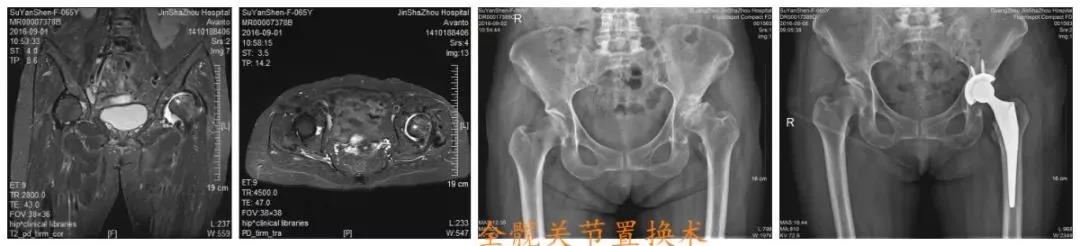

如果做了手术,比如关节置换,患者可以在短短几天后就下床,进行简单的活动,即使一些手术不能马上下床,但最起码可以在床上翻身、坐起。这些简单的动作可以有效的帮助患者把肺里的痰排出来,避免肺炎的发生,降低死亡率。